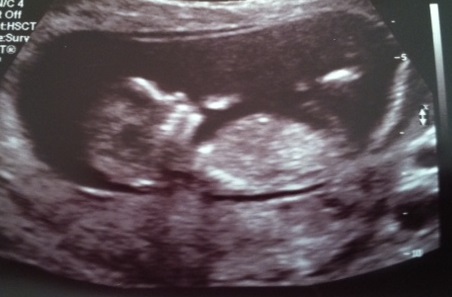

Hi! I had a scan yesterday, at 12 weeks + 2 days. The tech said the baby was measuring at 13 weeks.

I don't see a nub at all... unless I don't know what I am looking for, haha! Can anyone see anything and take a guess? Or maybe skull theory?

Attachment 15335